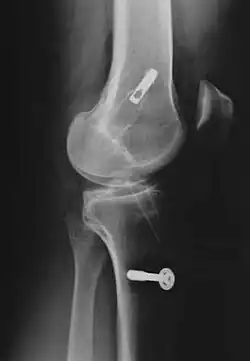

Grafts are inserted through a tunnel that is drilled through the shin bone (tibia) and thigh bone (femur). The graft is then pulled through the tunnel and fixated with screws. The two bright objects in this X-ray are screws in the thigh bone (above) and shin bone (below).